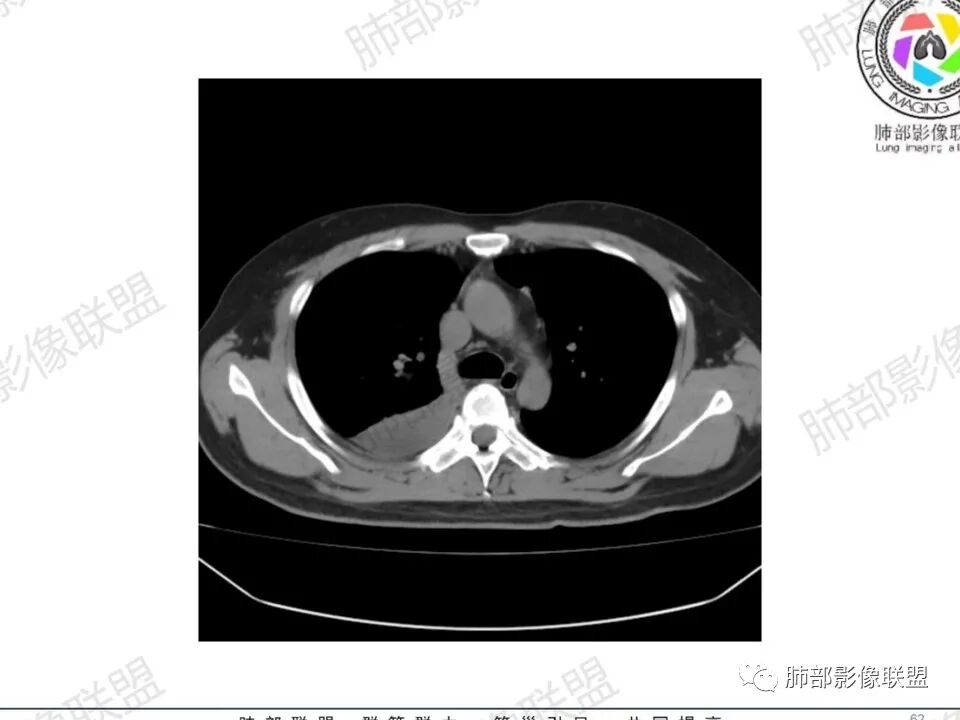

双肺多发结节,胸膜下为主,部分可见空洞。左肺上叶尖后段结节较大,分叶毛刺,周围可见长条索及小斑片影,内空洞比较光滑,内侧壁可见支气管通过。右肺下叶后基底段不张实变,后侧积液,右侧水平裂积液,右侧膈胸膜纵膈胸膜增厚积液,右侧侧胸膜肥厚,考虑1:一元金葡。2二元:金葡,左肺上叶结核。

中年男性,左手中指及胸壁疼痛伴发热来诊,影像见双肺多发结节,胸膜下分布为主,部分结节可见空洞,边缘模糊。左肺上叶尖后段结节较大。右肺下叶后基底段不张实变,右侧叶间裂及右侧胸腔积液,右侧侧胸膜肥厚。考虑金葡菌感染,血播SPE。